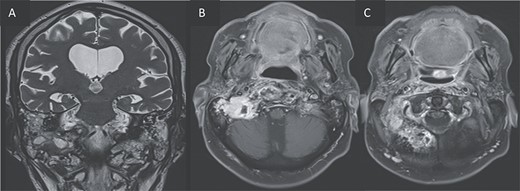

Axial CT in bony window showing: (A, B) extensive bone erosion of the clivus and the body and right greater wing of the sphenoid. (C) Soft tissue in the middle ear cavity and mastoid cells.